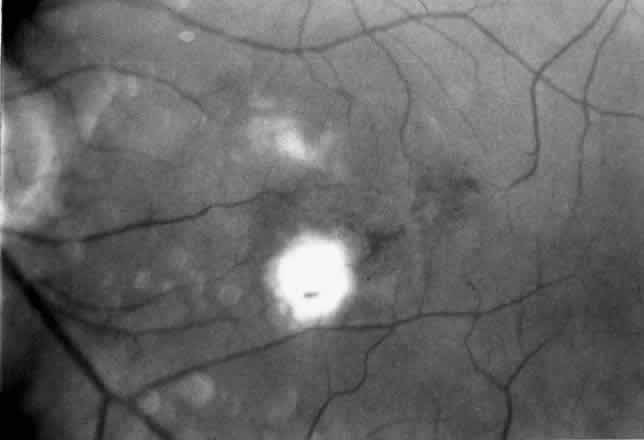

2. A 35-year-old patient developed an idiopathic subfoveal choroidal neovascular membrane with decrease in vision to 20/200 (6/60) (Fig. 9). He underwent surgical excision of the membrane. Laser was applied to the retinotomy at the conclusion of the case. One year after surgery, his visual acuity remained stable at 20/20 (6/6) (Fig. 10).

Fig. 9. Preoperative fundus photograph of a 35-year-old patient with idiopathic subfoveal neovascularization (case 2). Visual acuity is 20/200 (6/60).